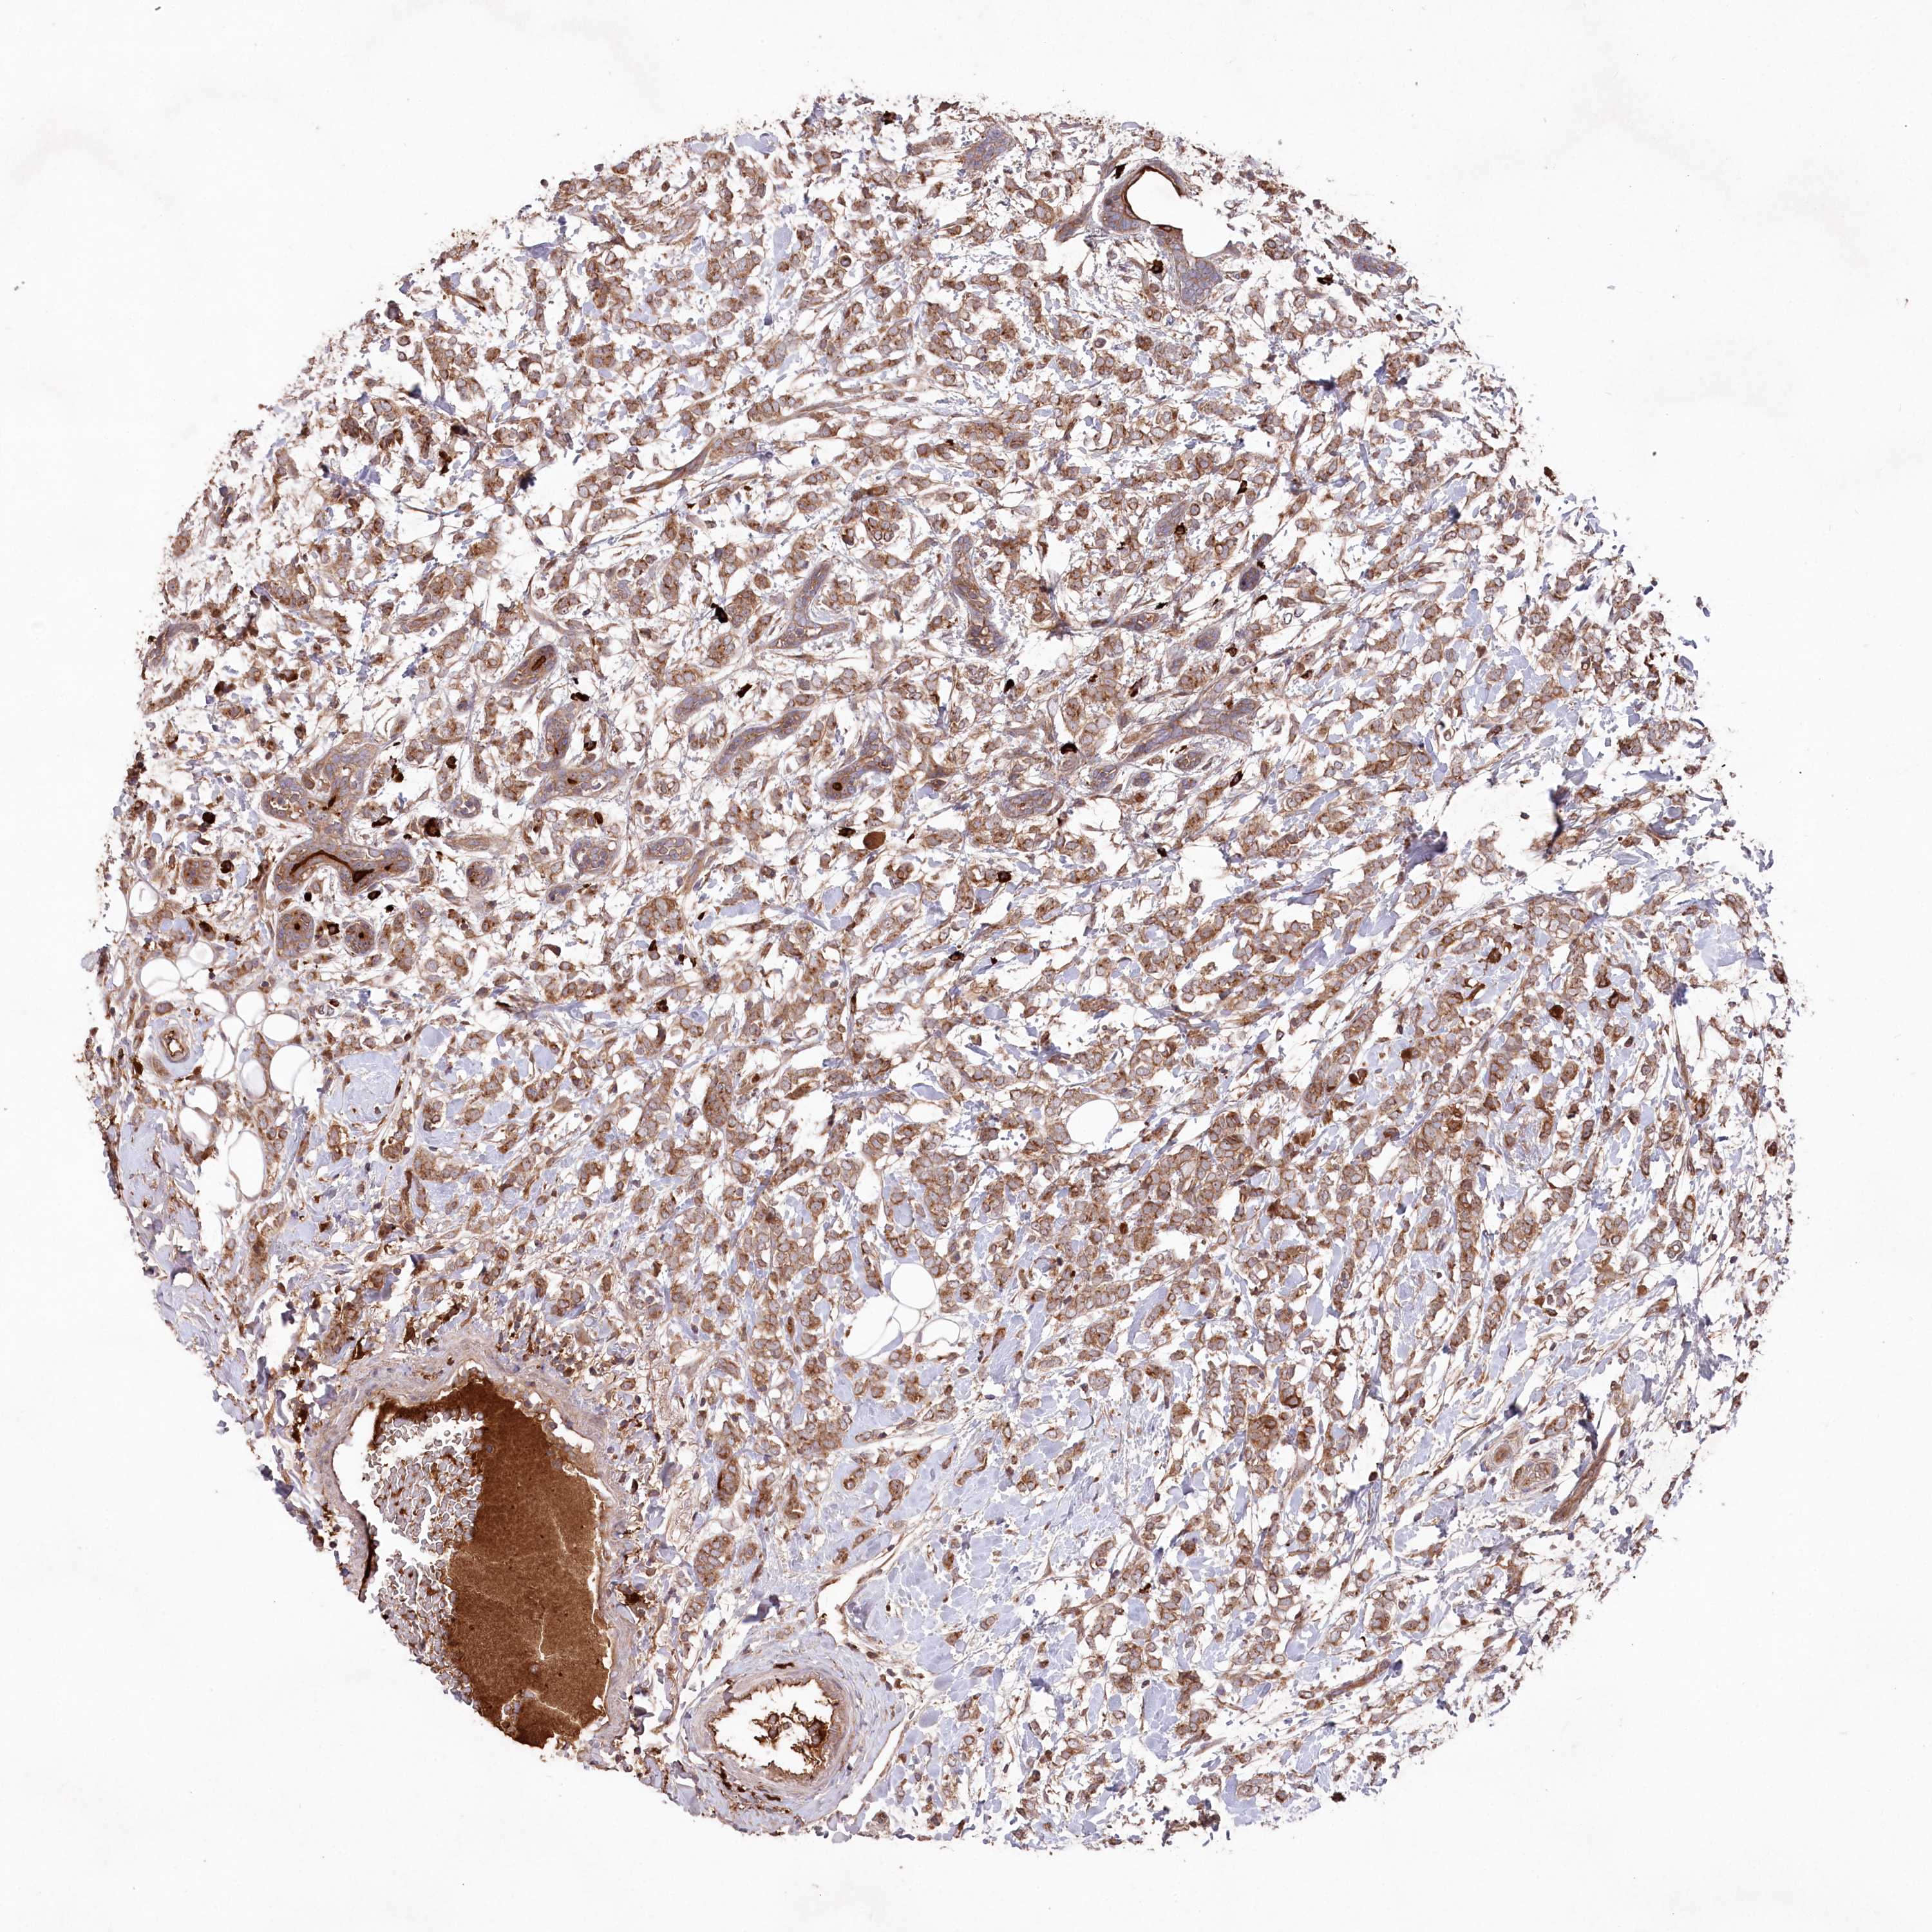

CANCER BREAST CANCER Show tissue menu

BRCA TCGA BRCA VALIDATION PROTEIN EXPRESSION

ANTIBODIES

AND

VALIDATION